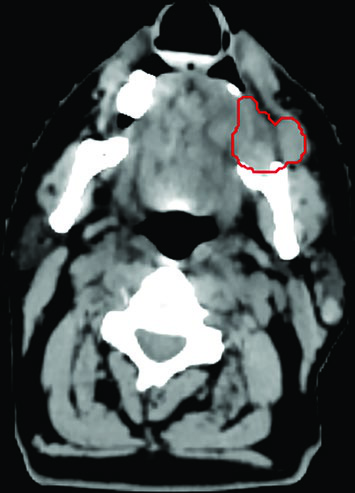

An illustrative case is an 83-year-old woman, previously treated surgically for right tongue squamous cell carcinoma, who presented 3 years later with a painful right level II nodal mass deep to the parotid, extending into the parapharyngeal space and carotid sheath. She was not a candidate for radical chemoradiation and received 45 Gy in 5 fractions, twice weekly. GTV delineation (red) was aided by CT-MRI fusion, with CT on the left and MRI on the right displayed on the same planning screen.

While her pain improved, MRI at 4 months showed possible progression on T1 but response on T2 — discordant findings that could lead to a premature salvage decision if interpreted in isolation. At 9 months, MRI demonstrated disease stability and the patient was pain-free. This case reinforces that multiparametric assessment and patience are essential in post-SBRT follow-up.